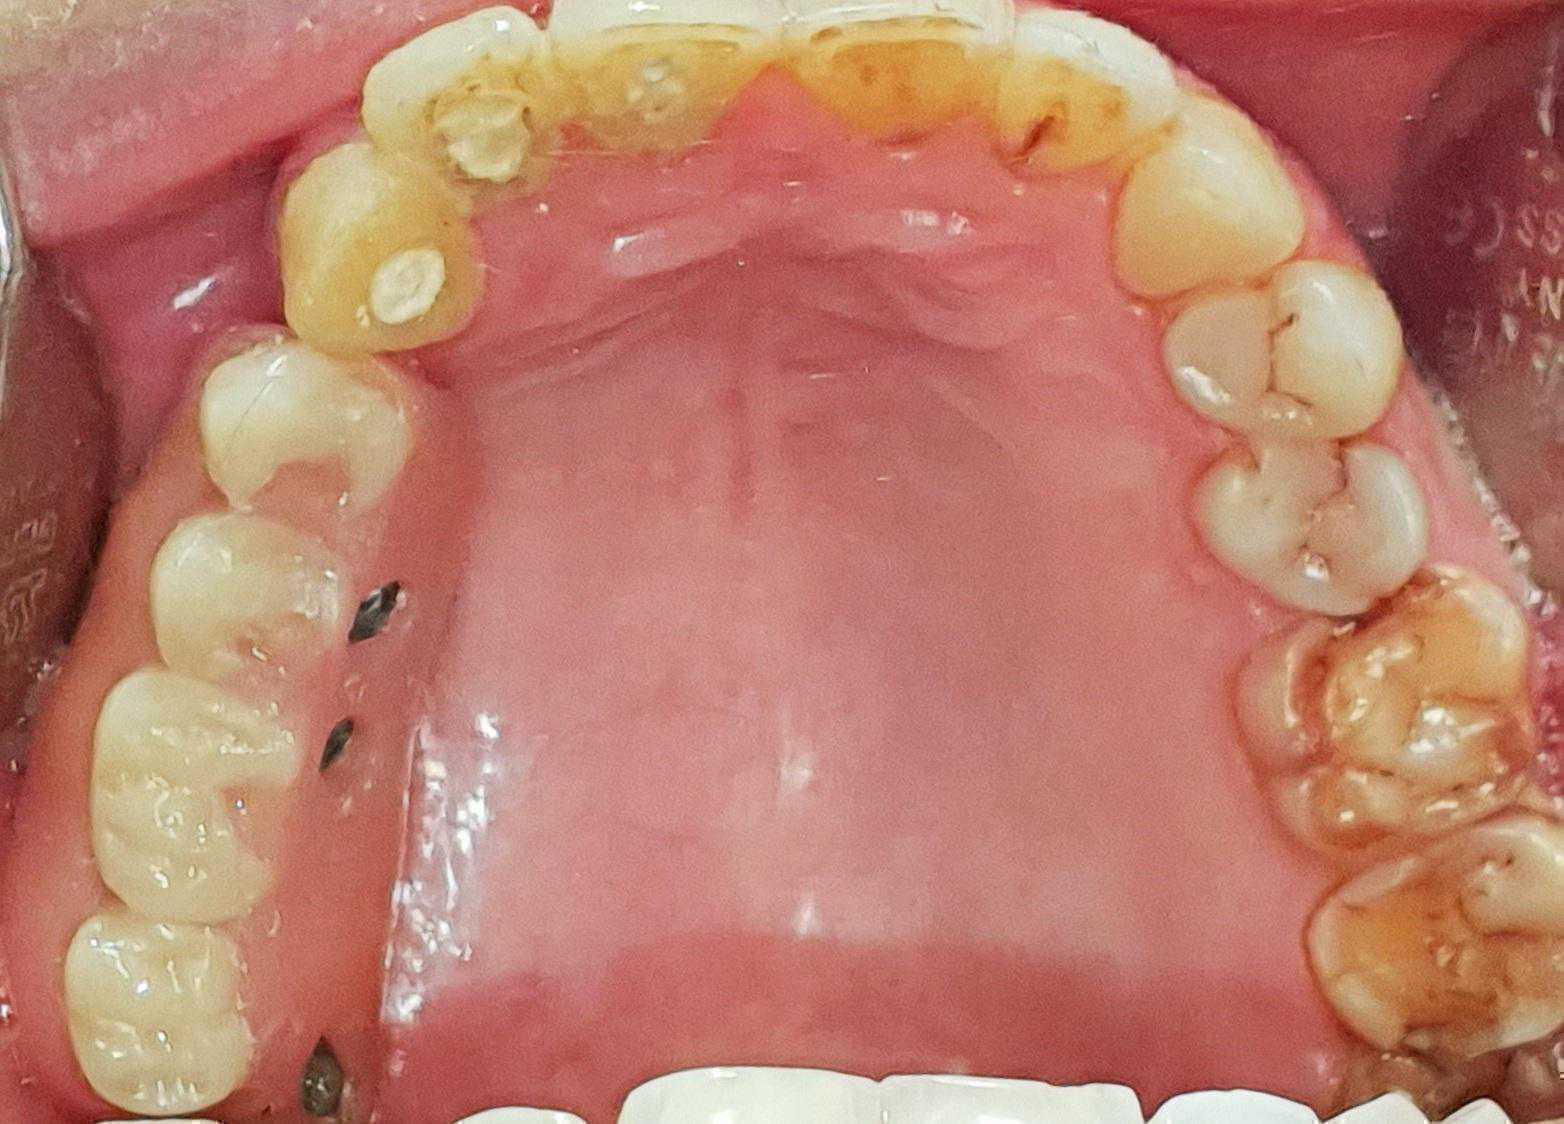

https://demo.discussdentistry.com/forums/topic/post-mucormycosis-avascular-necrosis-of-maxilla-rehabilitation-with-zygomatic/#post-24499 <![CDATA[Post Mucormycosis Avascular necrosis of maxilla, rehabilitation with Zygomatic]]> https://demo.discussdentistry.com/forums/topic/post-mucormycosis-avascular-necrosis-of-maxilla-rehabilitation-with-zygomatic/#post-24499 Thu, 25 Aug 2022 12:14:40 +0000 Sankalp Mittal

• 20210604_101325 (2)20210604_101317 (2)20210604_103315 (2)20210604_102857 (2)20210604_104202 (2)20210604_104853 (2)20210824_105656 (2)20210824_112353 (2)20210824_114957 (2)20210824_131302 (2)20210826_100648 (2)20210826_100749 (2)20210826_100919 (2)20210914_183943 (2)20211001_17535220211012_18543620211012_192043 (2)20211012_185627 (2)20211012_195430 (3)20211027_193725 (2)20211027_200729 (2)20211027_200919